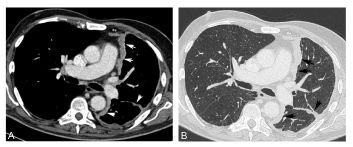

Fig. 95.4. Mésothéliome pleural gauche.

Tomodensitométrie en fenêtre médiastinale (A) et pulmonaire (B) après injection de produit de contraste. Il existe un épaississement irrégulier et nodulaire de la plèvre de l’hémithorax gauche prédominant sur la plèvre médiastinale (flèches). L’épaississement se prolonge vers la grande scissure gauche (flèches). Notez la rétraction de l’hémithorax gauche.

Source : CERF, CNEBMN, 2022.